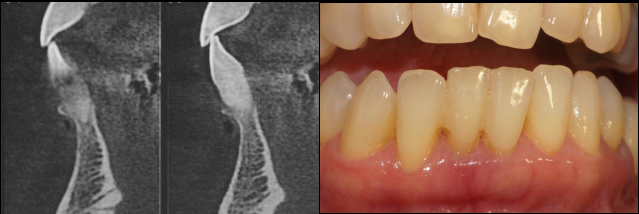

Paciente do sexo feminino, 65 anos, compareceu na clínica com o elemento 41fraturado. Porém, o fragmento estava estabilizado com resina acrílica, unindo-o aos dentes adjacentes. Foi solicitado o exame tomográfico e a anamnese foi realizada. Ao examinarmos a tomografia, optou-se pela exodontia e as instalações imediatas do implante Maestro de 3.5 X 11 mm e de uma prótese adesiva para aguardar o período necessário para o carregamento do implante. A terapêutica medicamentosa utilizada foi a administração de antibiótico por sete dias, acompanhado do uso de anti-inflamatório durante três dias após o procedimento cirúrgico.

O fragmento coronário e a raiz residual foram removidos e após a curetagem do alvéolo iniciou-se a fresagem do mesmo, seguindo o protocolo de instalação do implante Maestro para o mesmo ser ativado de forma precoce (35 dias após a instalação). Utilizamos a fresa lança helicoidal e na sequência foi utilizada a fresa cônica de 3.5, ambas as fresas com rotação de 600 RPM. Após a fresagem, o implante Maestro de 3.5 X 11.0 mm foi inserido no alvéolo, atingindo um torque de instalação de 25 Ncm, seguindo assim o protocolo de instalação do implante Maestro para carga precoce. Na sequência, foi realizada a sutura e a prótese adesiva foi instalada.

Após 35 dias da instalação do implante foi realizada a abertura do implante através de um bisturi circular e o pilar Ideale reto de 3.3 X 4.0 X 2.5 mm foi torqueado no implante a 20 Ncm. Foi realizada também uma moldagem deste pilar com o seu transferente correspondente e a prótese adesiva voltou a ser instalada. Depois de uma semana, o provisório parafusado confeccionado no laboratório foi instalado e mantido em posição durante 15 dias para formar um novo perfil de emergência, aproximando as características dos tecidos circundantes às características de um incisivo central inferior. Neste momento, foi realizada uma nova moldagem da região e uma coroa metalocerâmica foi confeccionada e instalada após uma semana. Foi também realizada a radiografia.